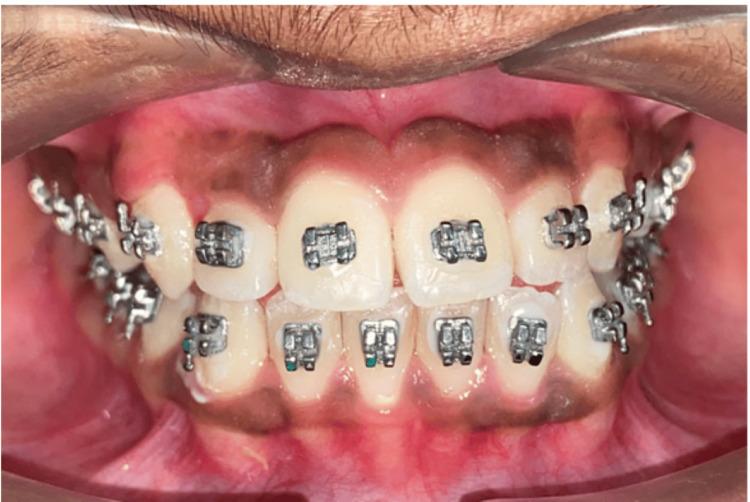

使用颏兜疗法对Ⅲ类错牙合伴前牙反牙合进行早期干预:病例报告

The Early Intervention of a Class III Malocclusion With an Anterior Crossbite Using Chincup Therapy: A Case Report.

Class III malocclusions with anterior crossbites pose significant challenges in orthodontic treatment, especially in growing children. This case report details the early intervention of a 12-year-old patient presenting with a Class III malocclusion characterized by an anterior crossbite and mandibular prognathism. A chincup was employed to inhibit mandibular growth and encourage maxillary development. Consistent use of the chincup, with regular follow-ups and adjustments, led to significant improvements. The anterior crossbite was corrected, resulting in a Class I molar relationship and an improved facial profile. The maxillary arch perimeter increased, providing space for the eruption of canines and premolars. This case demonstrates that early intervention with a chincup can effectively manage Class III malocclusion with an anterior crossbite, highlighting the importance of timely orthodontic assessment and treatment to achieve stable, long-term results.

摘要

伴有前牙反合的III类错颌畸形在正畸治疗中带来重大挑战,尤其是在生长发育期的儿童中。本病例报告详细介绍了一名12岁患有III类错颌畸形患者的早期干预情况,其特征为前牙反合和下颌前突。使用颏兜来抑制下颌生长并促进上颌发育。持续使用颏兜并定期随访和调整,带来了显著改善。前牙反合得到纠正,形成了I类磨牙关系并改善了面部轮廓。上颌牙弓周长增加,为尖牙和前磨牙的萌出提供了空间。本病例表明,早期使用颏兜干预可有效治疗伴有前牙反合的III类错颌畸形,凸显了及时进行正畸评估和治疗以获得稳定长期效果的重要性。